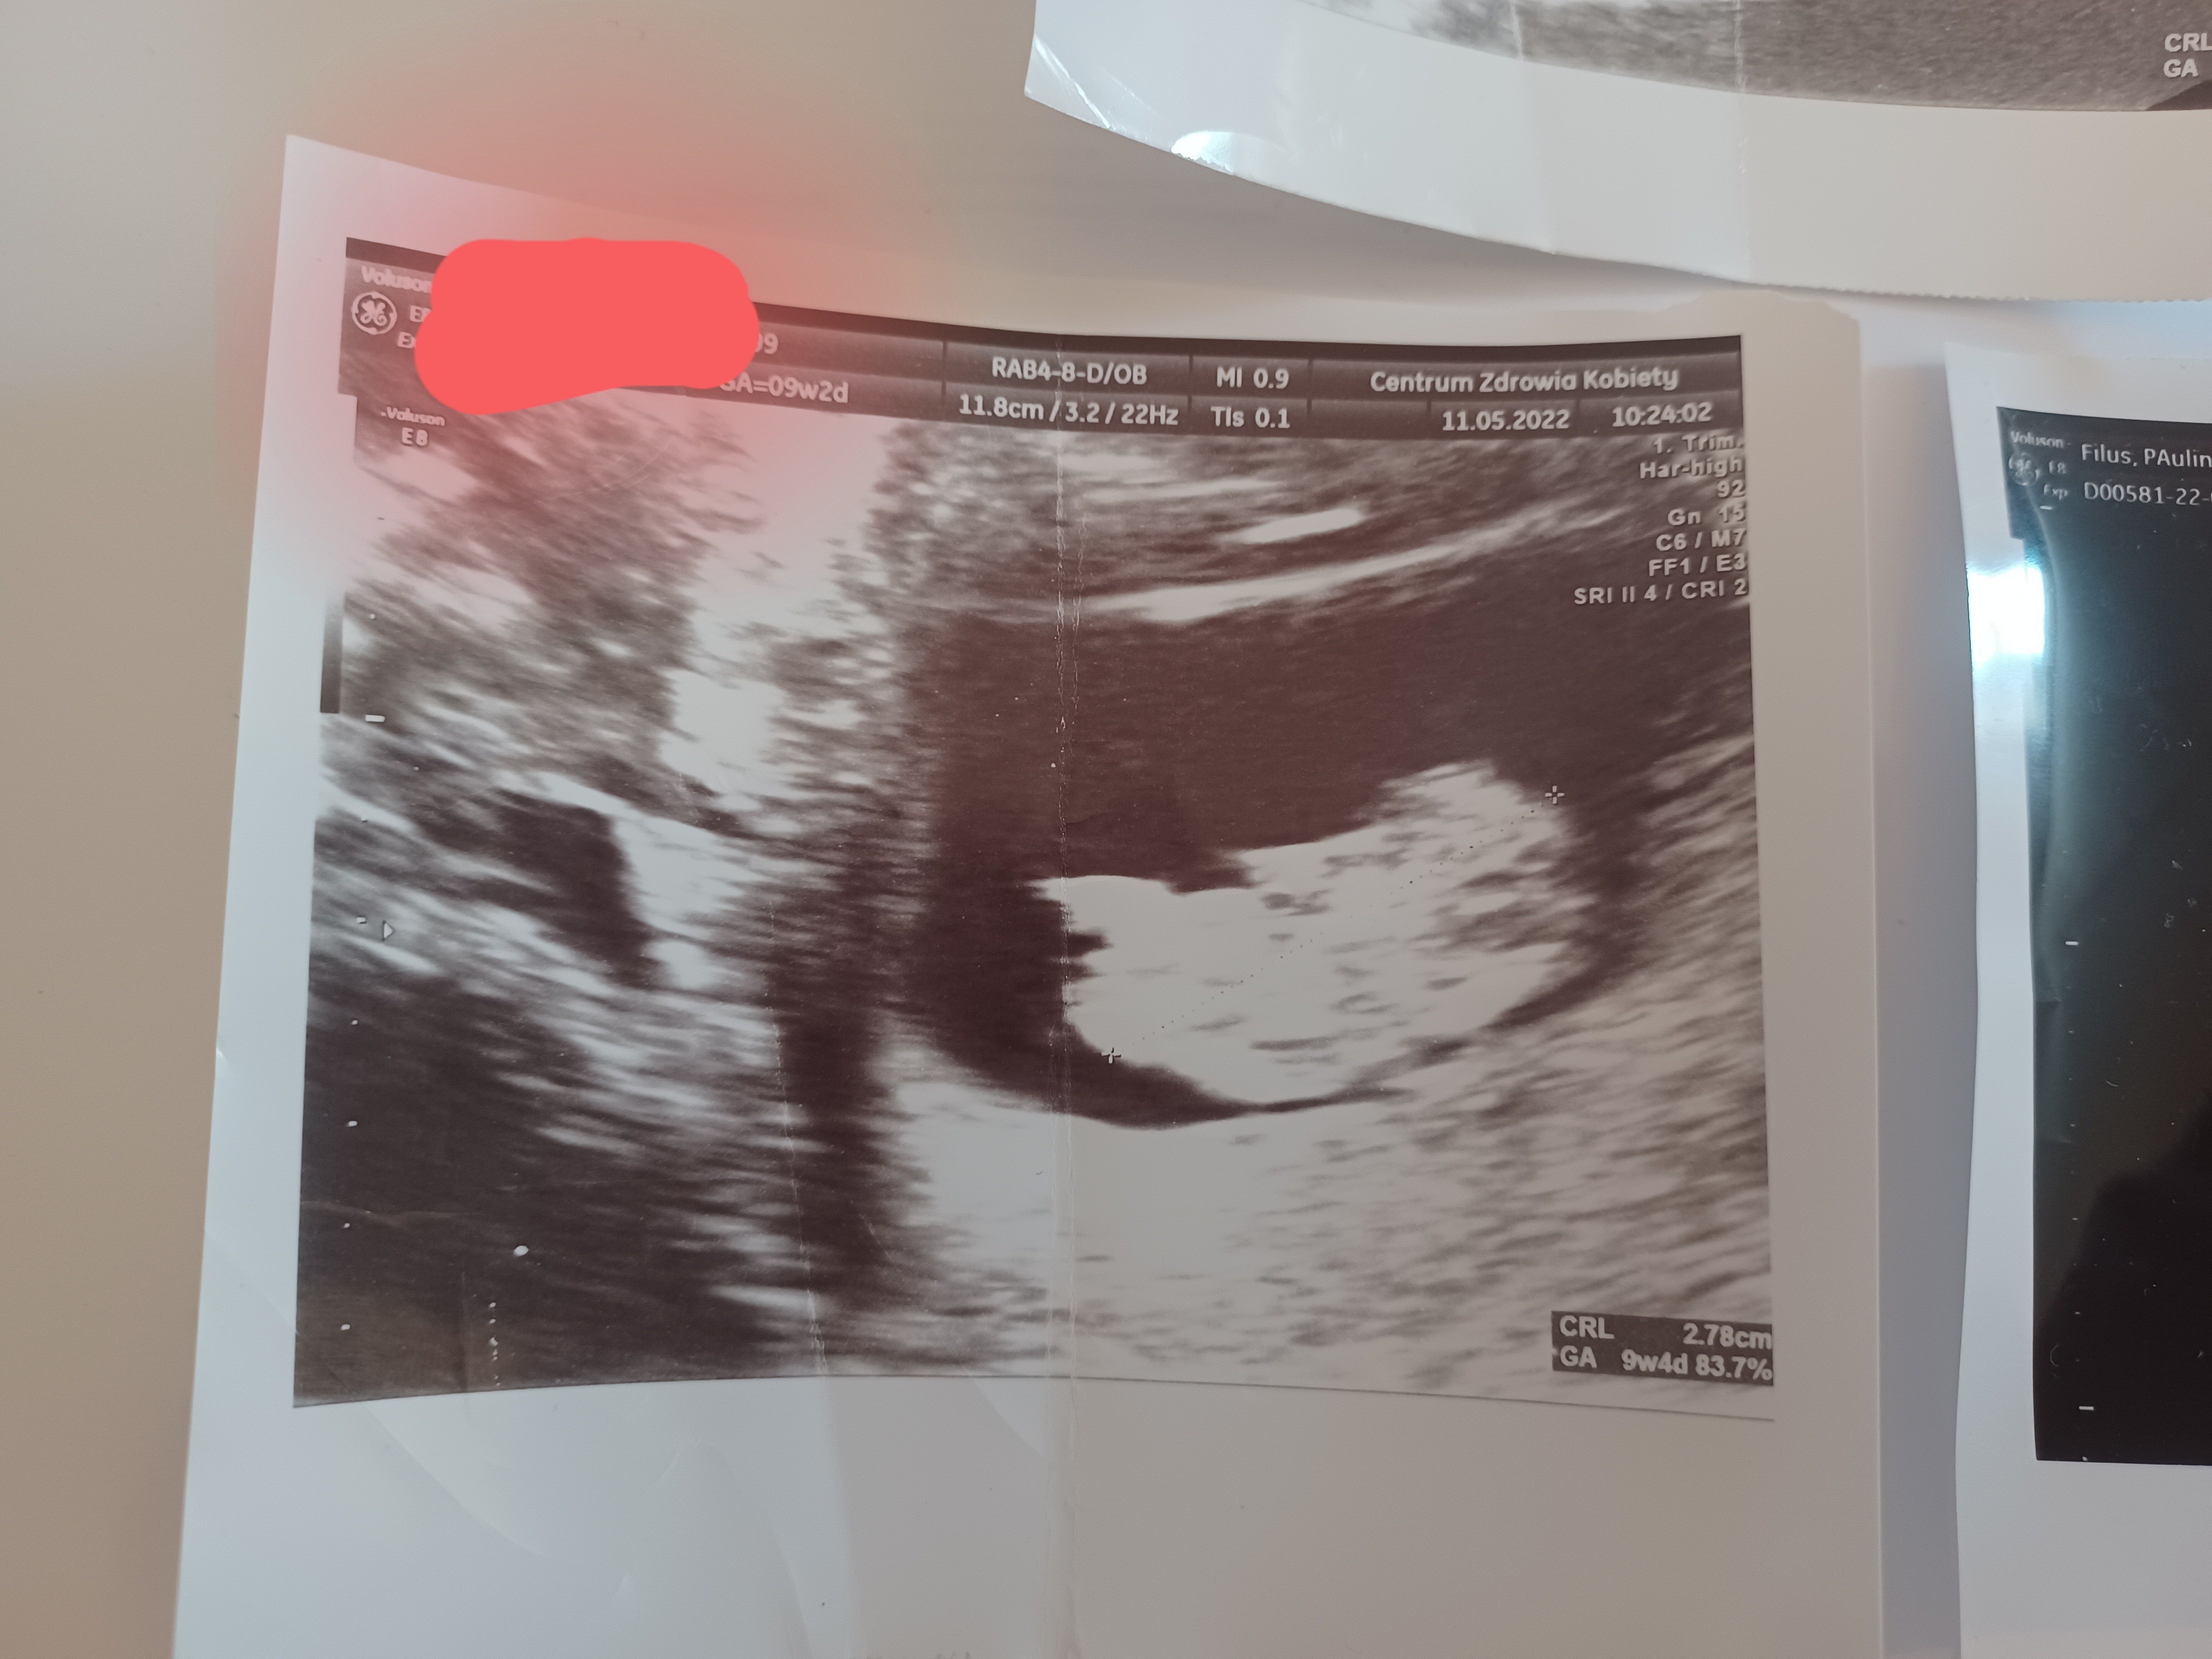

Hej dziewczyny czy jesteście w stanie przypuszczać po tych usg jaka to płeć dziecka? Mam przeczucie ze to chłopiec a jak waszym zdaniem? To wszystkie usg jakie posiadam.

• 20220713_175959.jpg

20220713_175959.jpg

1,5 MB · Wyświetleń: 461